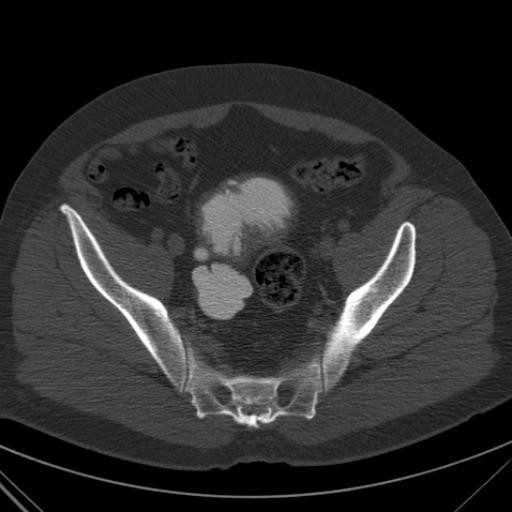

КТ-исследование абсцесса малого таза: Визуализация и диагностика

Раздел: Фотоальбом решений